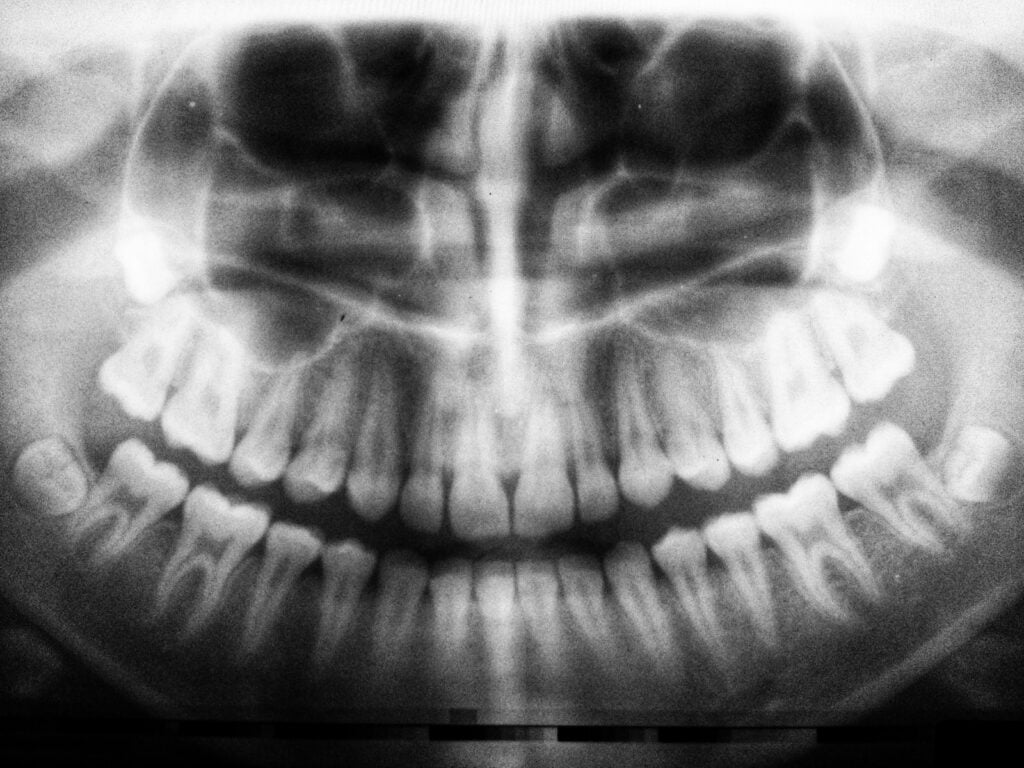

Перед операцией по уменьшению подбородка очень важно записаться на консультацию к квалифицированному пластическому хирургу. Во время первой встречи хирург оценит анатомию вашего лица, обсудит ваши эстетические цели и определит наиболее подходящий хирургический подход для ваших конкретных потребностей. Они могут использовать технологию компьютерной визуализации, чтобы обеспечить визуальное представление потенциальных результатов.

В случаях, когда подбородок слишком выступает, хирург может выбрать уменьшение кости. Во время этой техники хирург осторожно удаляет часть кости подбородка, чтобы добиться желаемого уменьшения размера. Они моделируют кость, чтобы создать более пропорциональную и гармоничную форму подбородка.

Людям с утопленным или недоразвитым подбородком может быть рекомендовано наращивание кости. Этот метод предполагает использование имплантатов или костных трансплантатов для увеличения размера и проекции подбородка. Хирург тщательно выберет и расположит имплантат или материал трансплантата для достижения желаемого результата.